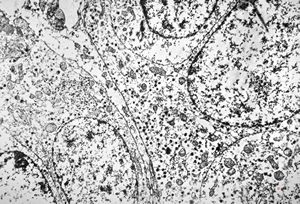

M,50y. | Pneumocystis carinii - lung